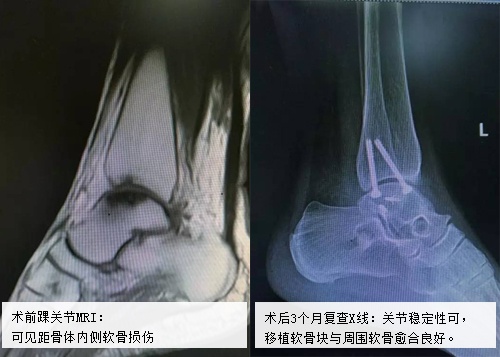

大河健康网讯(记者:王芳芳 通讯员:任浩然)踝关节是人体下肢重要的负重关节,当踝关节发生外伤时,若得不到及时正确的治疗,或会引发创伤性关节炎甚至距骨软骨坏死,导致踝关节疼痛,影响正常活动。 今年54岁的吴阿姨就是这样一个例子。据记者了解,早在2008年,吴阿姨左踝关节因受到外伤出现疼痛,保守治疗了一段时间,但没有彻底治愈,活动时仍有疼痛。5年来吴阿姨到处寻医,每一天都在遭受疼痛的折磨,直到2013年,吴阿姨听说河南省中医院关节科主任王上增教授擅长治疗关节类疑难疾病,就抱着试试的态度来治疗。 2013年6月16日,在仔细观看吴阿姨的片子后,王上增教授告诉她:“你这是由于外伤造成的踝关节外侧韧带损伤,这样一来,踝关节外侧长期不稳定,就导致了距骨软骨缺血性坏死,所以会出现踝关节疼痛及活动受限的症状。”而解决的主要办法,就是在重建踝关节稳定性的同时,让坏死的距软骨重获新生。 “考虑到病人的膝关节功能好,软骨形态正常,我们采取了‘移花接木’的方式,也就是说从患者膝关节股骨外髁处截取不负重的一处软骨块,然后移植替代坏死的距骨。”王上增主任说。手术由王上增主任及该科郑永智大夫等医生,共同完成。 据悉,这是省内为数不多的“关节镜辅助下距骨坏死清理软骨移植及外侧副韧带修补术”,术后约20天,吴阿姨顺利出院,告别了病痛的折磨。

2016年10月8日,国庆假期结束后的第一天,吴阿姨又来到这里。“感谢王主任精湛的技术,我现在左踝关节感觉非常好,也不疼了。我这次来想让你们看看我的右踝关节,最近这俩月它一直疼,什么方法都试了可还是不缓解,想让主任你们也通过手术解决我的右踝关节问题。”吴阿姨向该科贺自克大夫解释。 王上增教授看了吴阿姨右踝关节的片子后,表示:“患者右踝关节疼痛的原因也是距骨软骨坏死,但与左侧不同的是右踝关节的稳定好,可以采用和左踝相同的手术方式来治疗,只不过不用重建外侧副韧带了,这样手术就相对简单很多了。” 就这样,在王上增教授及科室团队的共同协作下,吴阿姨的右踝也成功完成“关节镜辅助下距骨坏死清理并踝关节软骨移植术”。